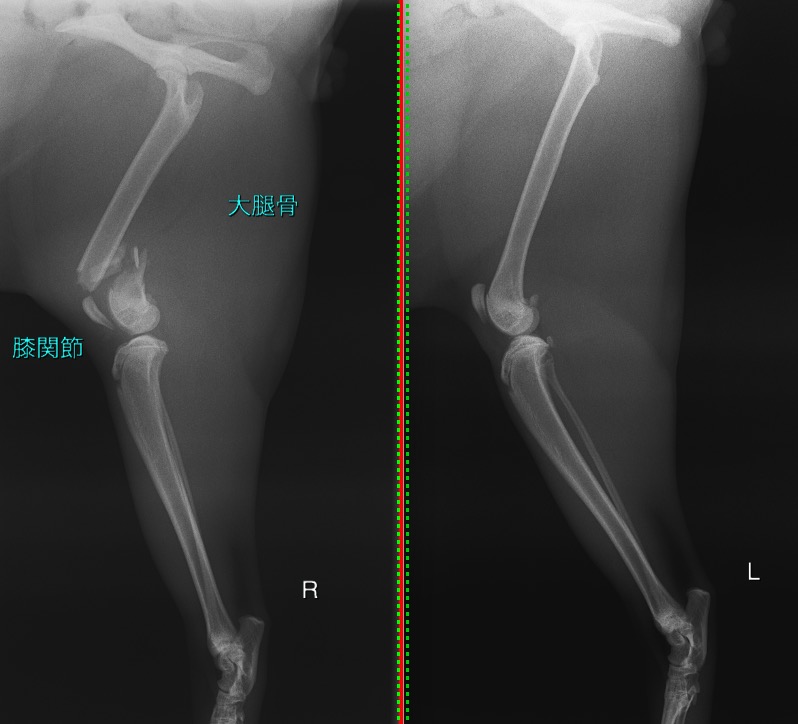

右の大腿骨(太ももの骨)の遠位(膝の関節に近い部分)が粉砕骨折(骨片が3つ以上に砕けてしまう骨折)してしまっていました。

正常肢と比べると、膝の関節に近い部分の骨が折れてしまっているのが分かります。

骨折の見られる右後肢/正常な左後肢

CTによる3D像 骨折の見られる右後肢/正常な左後肢